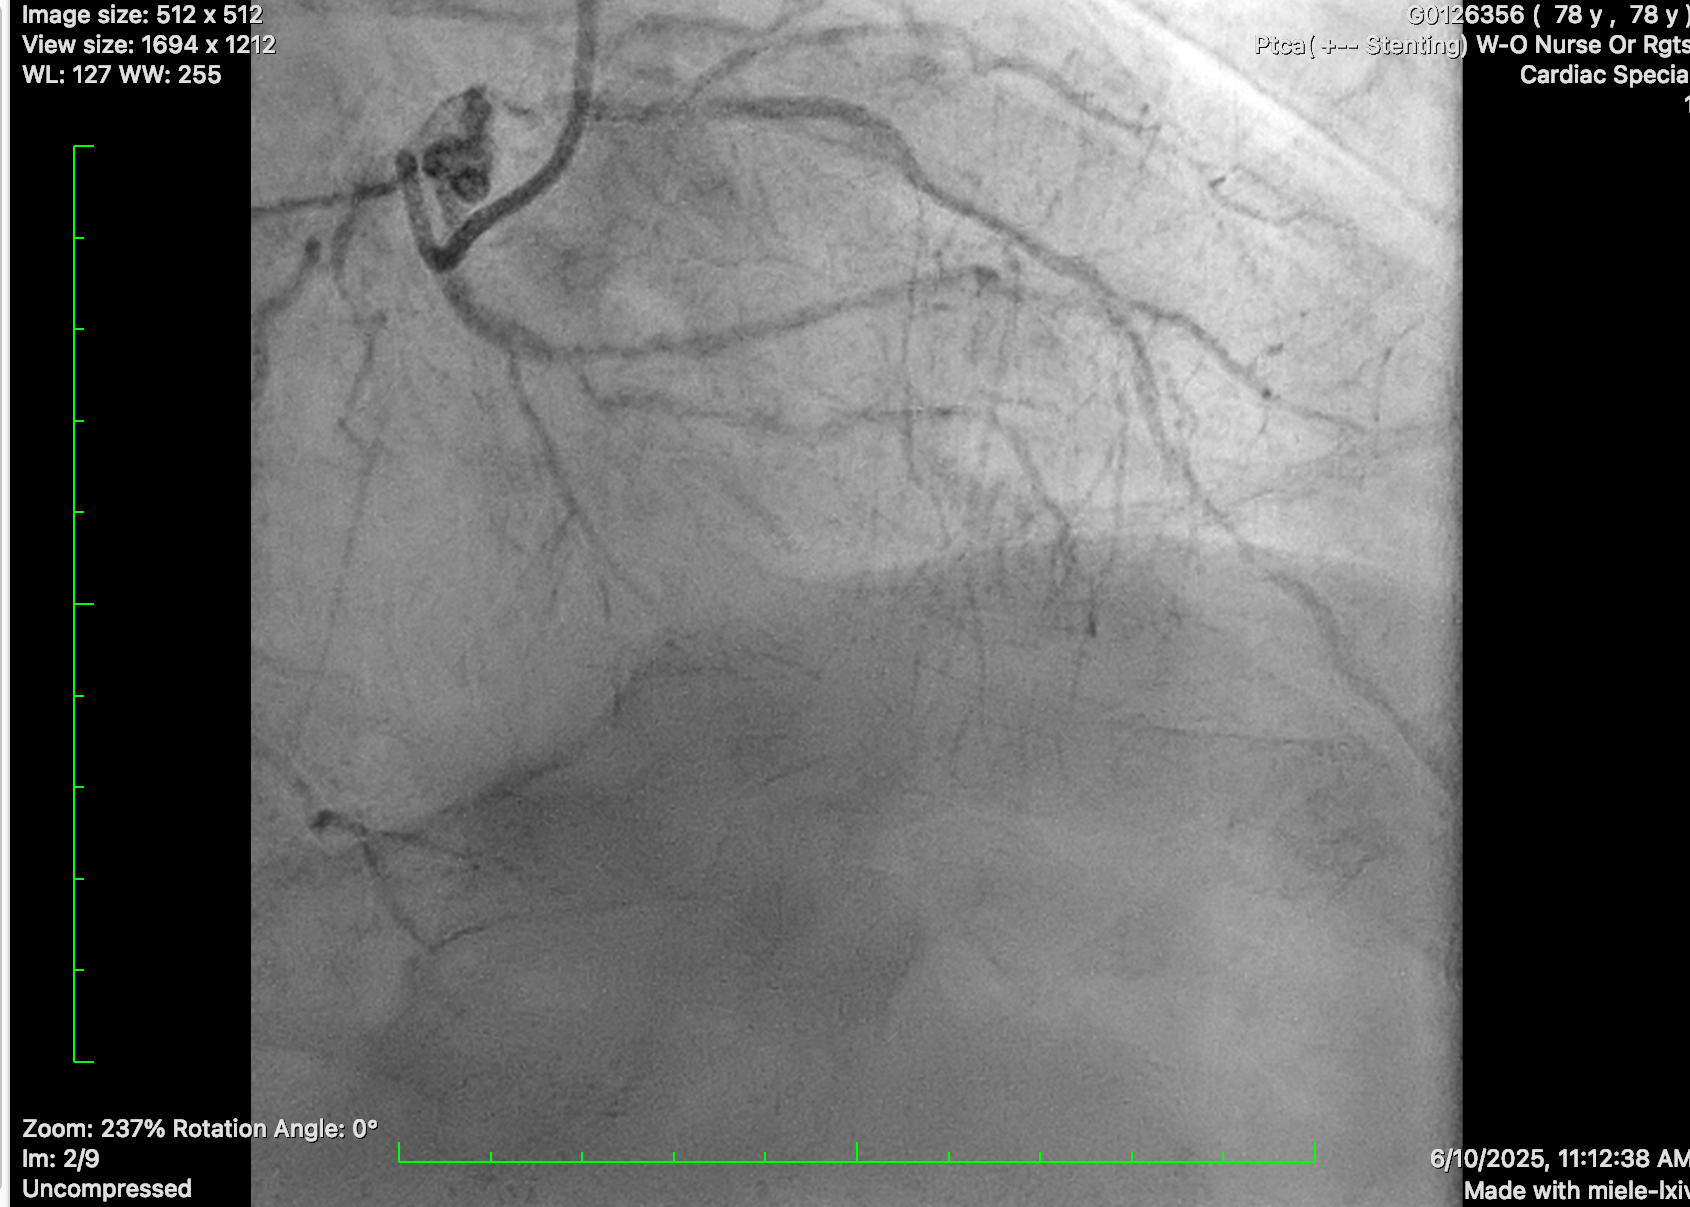

Diagnostic coronary angiogram was performed, showing distal left main disease and ostial LAD subtotal occlusion with antegrade flow, diffuse severe disease over proximal to mid LAD. Mid-LCx showed severe stenosis. RCA was dominant, with mRCA severe disease followed by subtotal occlusion with antegrade collateral to distal RCA and retrograde collateral to septal branches of LAD and diffuse severe disease at PL branch.